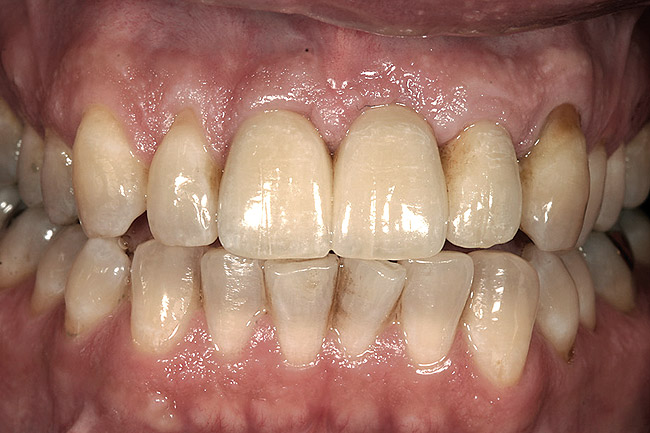

Figure 5  A patient presented needing both centrals extracted. Note the excellent papillary height and free gingival margin location.

Figure 5

Figure 6  Excellent interproximal crestal bone level between the centrals before extraction.

Figure 6

Figure 7  Because the interproximal crestal bone was maintained and the soft tissue supported at the time of tooth removal, an excellent interimplant papilla exists.

Figure 7

Figure 8  Maintenance of interproximal crestal bone following final restoration placement.

Figure 8

Figure 9  The final restorations exhibit a minimal 1-mm to 1.5-mm change in papilla height when compared with the pre-extraction height.

Figure 9